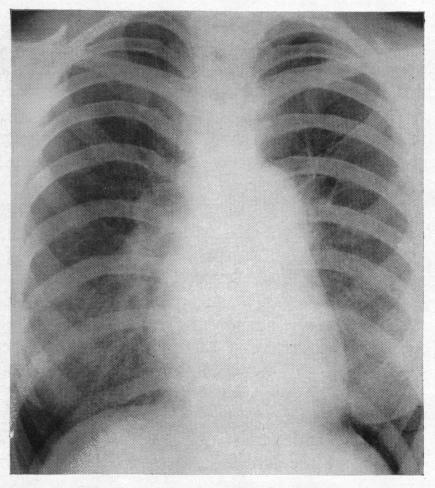

Solitary pulmonary hypertension.

Br Heart J. 1957 Jan;19(1):93-116. doi: 10.1136/hrt.19.1.93.